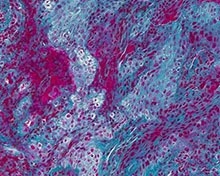

Disarming a Blood-Clotting Protein Prevents Gum Disease in Mice

Blood clotting

In a study published in Science, a team led by NIDCR’s Niki Moutsopoulos, DDS, PhD, and Thomas Bugge, PhD, found that buildup of a blood-clotting protein, called fibrin, triggers an overactive immune response that damages the gums and underlying bone. By blocking fibrin's function, the researchers prevented bone loss in mice with gum disease.